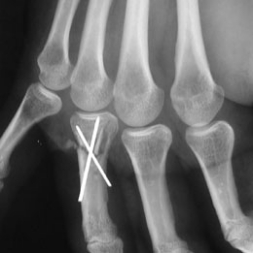

B - Radiographie de 3/4 : Pas d'ostéolyse autour du matériel. Les broches ne traversent pas la surface articulaire métacarpo-phalangienne.

Contrôle d'un brochage phalangien.